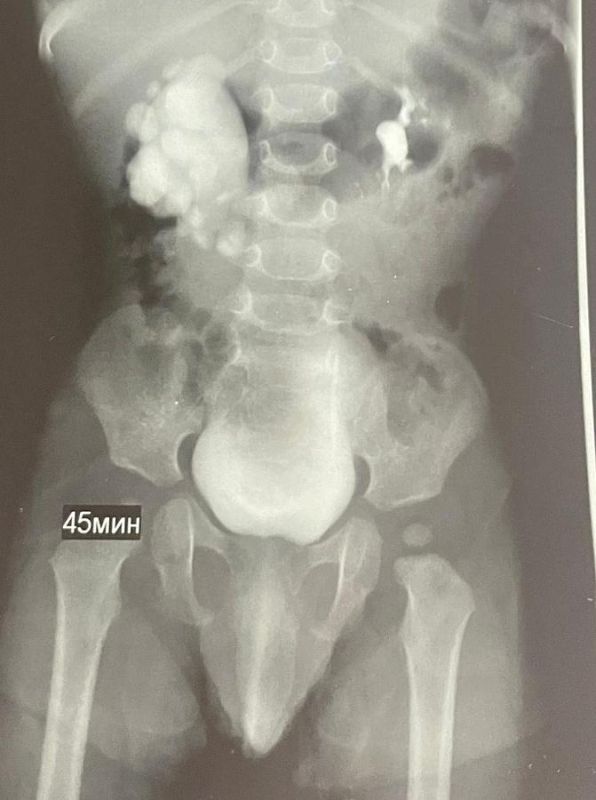

Патологию заметили ещё во время беременности мамы малыша, а сразу после его рождения специалисты взяли ребенка под наблюдение. Весной 2025 года обследование показало: у мальчика — гидронефроз. При этом заболевании почка...